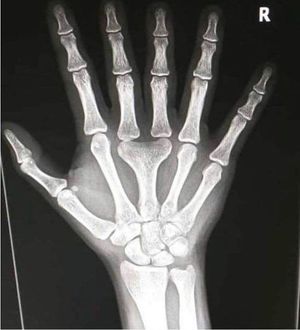

What is the name of this condition??

Polydactyly